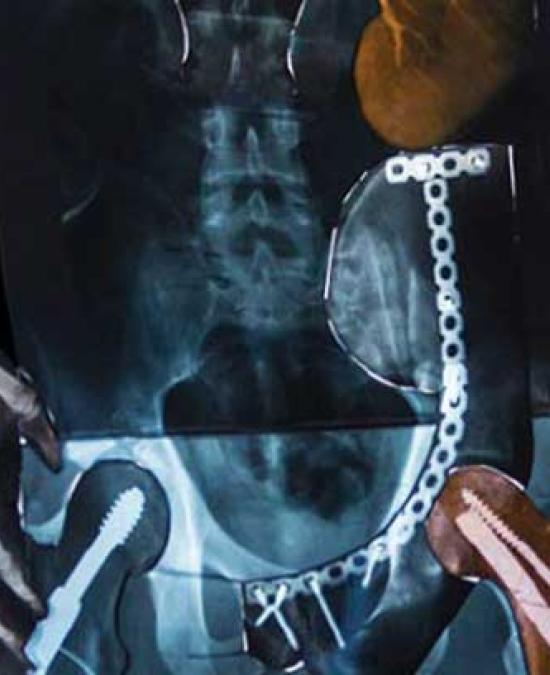

Hannah Dailey's novel orthopedic device may revolutionize bone fracture recovery, improving patient outcomes and reducing costs.